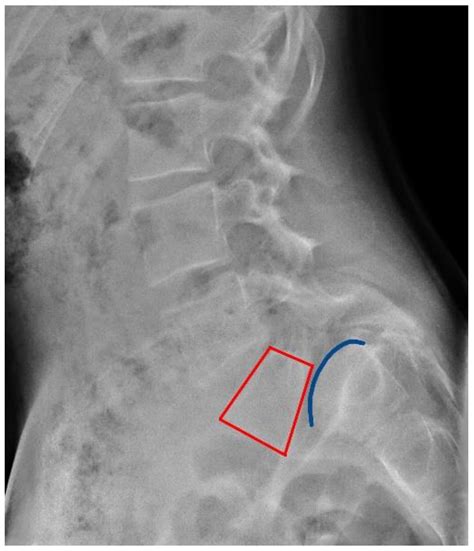

• Spondylolisthesis: This condition occurs when one vertebra slips forward over another, often due to a defect or fracture in the pars interarticularis, a small bone in the spine. Spondylolisthesis can cause instability in the spine and compress the nerves, leading to pain and other symptoms.

• Imaging Tests: X-rays, MRI, or CT scans can provide detailed images of the spine, helping to identify any abnormalities or damage to the L5 S1 disc.